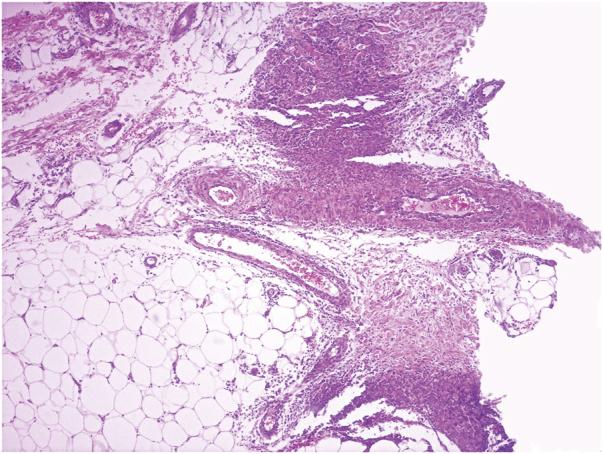

An Bras Dermatol. 2021 Sep-Oct;96(5):644-645. doi: 10.1016/j.abd.2020.07.021. Epub 2021 Jul 14.